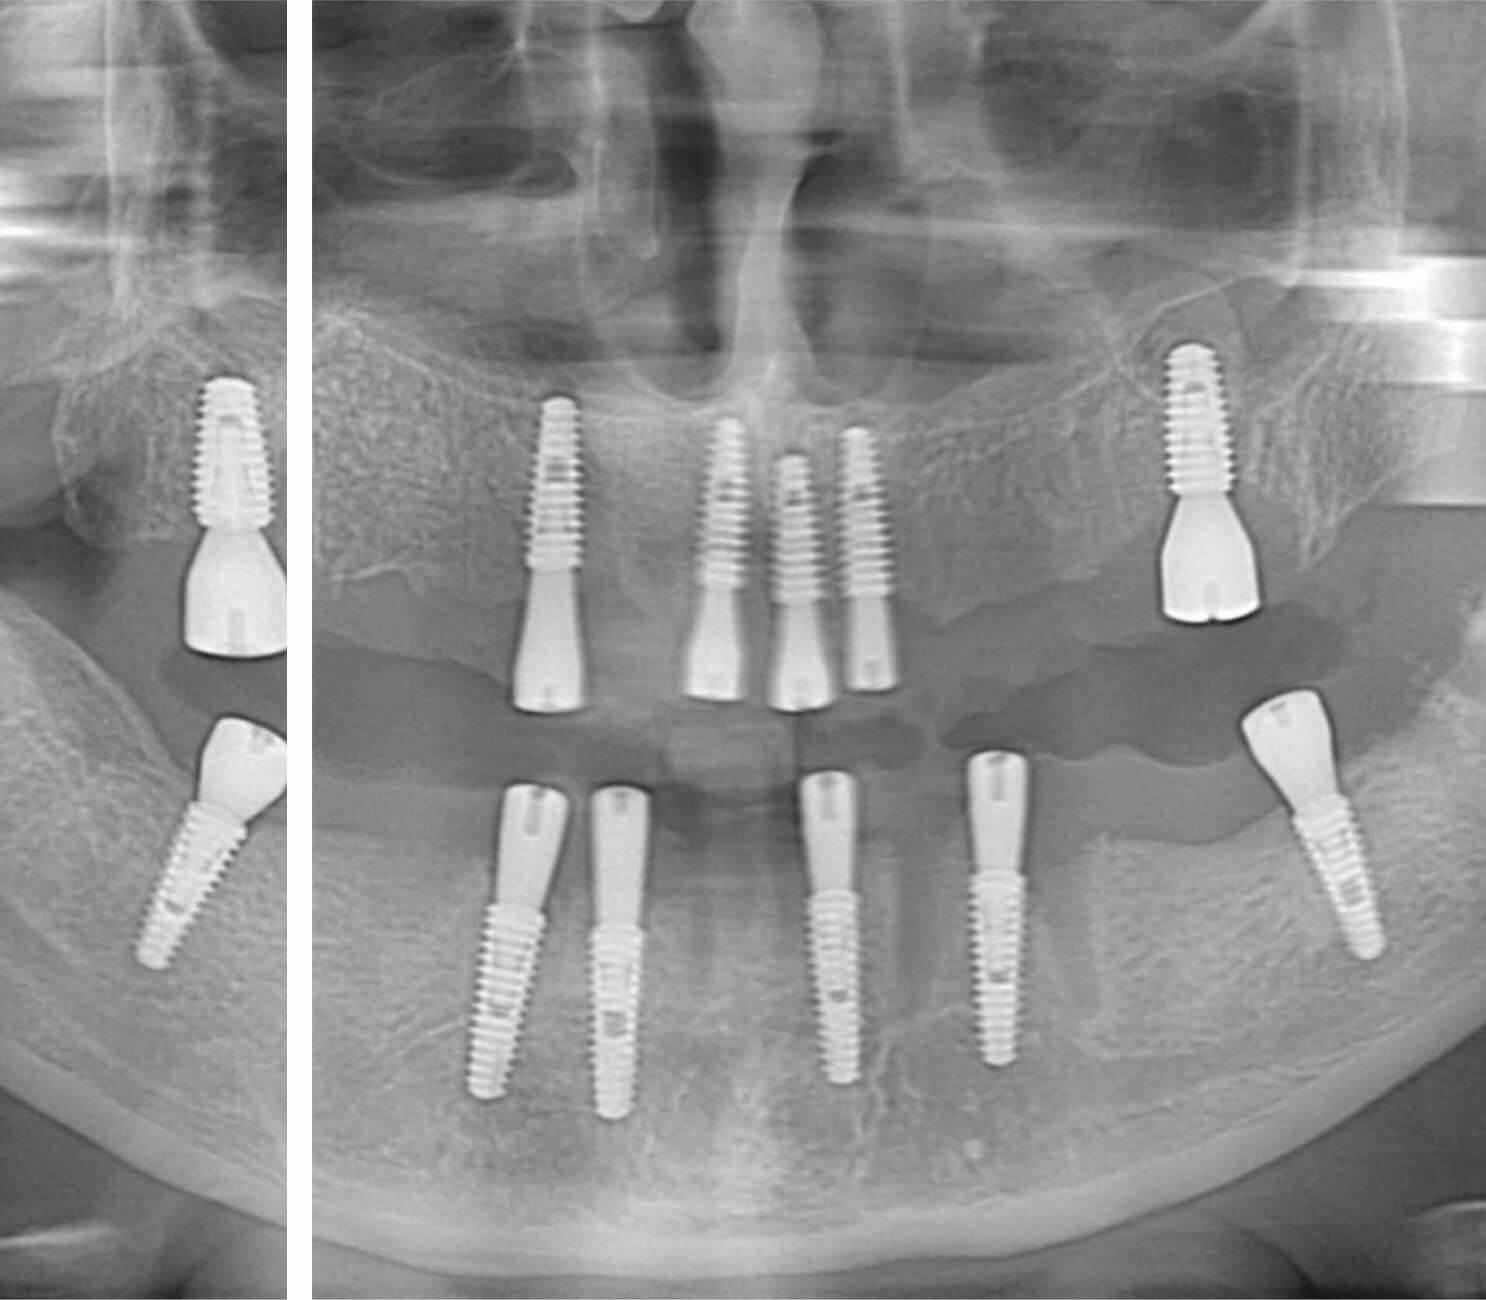

All On Six İmplant

6 implant ile daha güçlü altyapı, daha dengeli yük dağılımı. Özellikle üst çenede kemik desteğinin kritik olduğu tam dişsizlik vakalarında sabit ve uzun ömürlü protez çözümü. Tıbbi olarak incelenmiştir. Son güncelleme: 15 Nisan 2026.

Tam dişsizlik ya da çoklu diş kaybı yaşayan hastalarda sabit diş ihtiyacı yalnızca estetik değil, aynı zamanda fonksiyon ve yaşam konforu açısından da önem taşır. All On Six implant tedavisi, aynı çeneye yerleştirilen 6 implant üzerine planlanan sabit protez yaklaşımıyla daha güçlü bir altyapı oluşturmayı hedefler. Bu sayede çiğneme kuvvetlerinin daha dengeli dağıtılması, protezin daha sağlam desteklenmesi ve hastanın günlük yaşamda daha güvenli bir kullanım hissi elde etmesi amaçlanır.

All On Six implant, bir çenedeki tam dişsizliğin ya da kurtarılamayacak durumdaki dişlerin yerine, 6 implant yerleştirilerek sabit protez planlanması esasına dayanan bir tedavi yaklaşımıdır. Bu yöntem, uygun kemik desteğine sahip hastalarda sabit diş çözümü sunmak amacıyla değerlendirilir. İmplantların stratejik olarak yerleştirilmesiyle daha güçlü bir destek altyapısı oluşturulması hedeflenir.

Temel fark, protezi taşıyan implant sayısıdır. All On Six’te 6 implant kullanılır, yine adı üzerinde All On Four'da da 4 implant kullanılır. Hangi yaklaşımın uygun olduğu hastanın kemik yapısı ve tedavi planına göre belirlenir.

Tam dişsizlik durumunda her eksik dişe ayrı implant yerleştirmek teorik olarak mümkün olsa da, bu yaklaşım 10-14 implant anlamına gelir: hem cerrahi yük hem maliyet hem de iyileşme süresi çok artar. All-on-6 yöntemi, stratejik olarak yerleştirilmiş 6 implant üzerine tam ark sabit protez monte ederek aynı fonksiyonel sonucu çok daha az cerrahi müdahale ile elde eder.